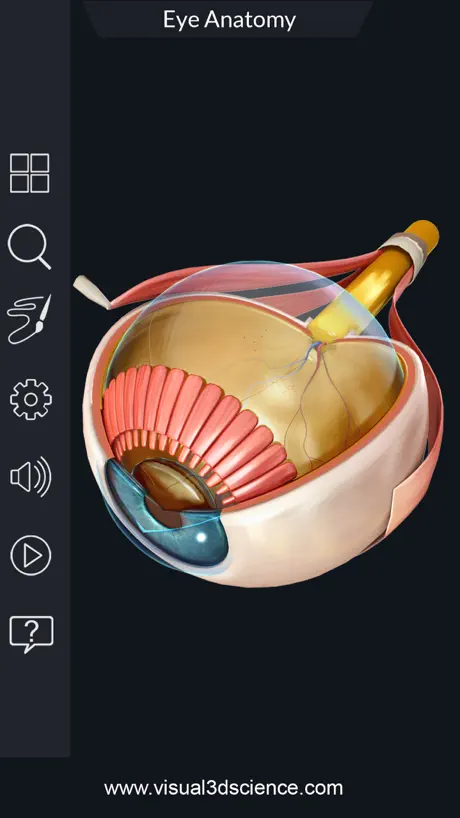

Screenshots